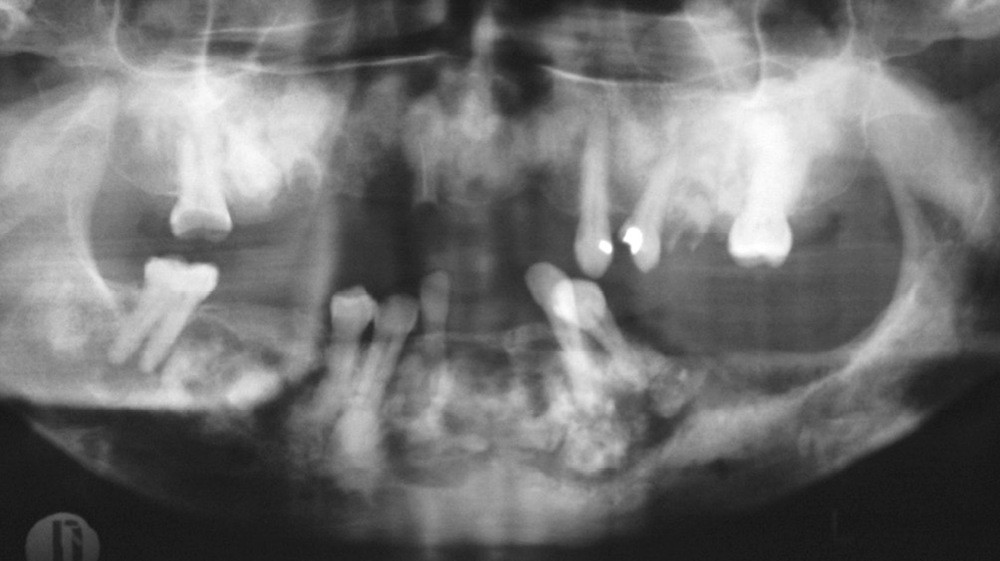

1. Dysplasie cémento-osseuse (DCO) de type floride au stade d’ostéomyélite.

• La dysplasie cémento-osseuse est une lésion fibro-osseuse rare de la mâchoire qui peut affecter certains secteurs (forme péri-apicale), ou les quatre cadrans (forme floride) (fig. 1). Au niveau radiologique, elle se caractérise dans cette dernière, par de multiples lésions osseuses denses et lobulées, souvent situées de manière symétrique dans plusieurs régions de la mâchoire (fig. 2). Ces lésions osseuses prédisposent au développement d’ostéomyélite maxillo-mandibulaire notamment en cas de geste invasif exposant l’os ou en cas d’infection dentaire. S’il est clairement contre-indiqué de recourir à la chirurgie implantaire dans les zones atteintes par la DCO, il pourrait en revanche être envisageable de poser des implants dans les zones indemnes [19,20].